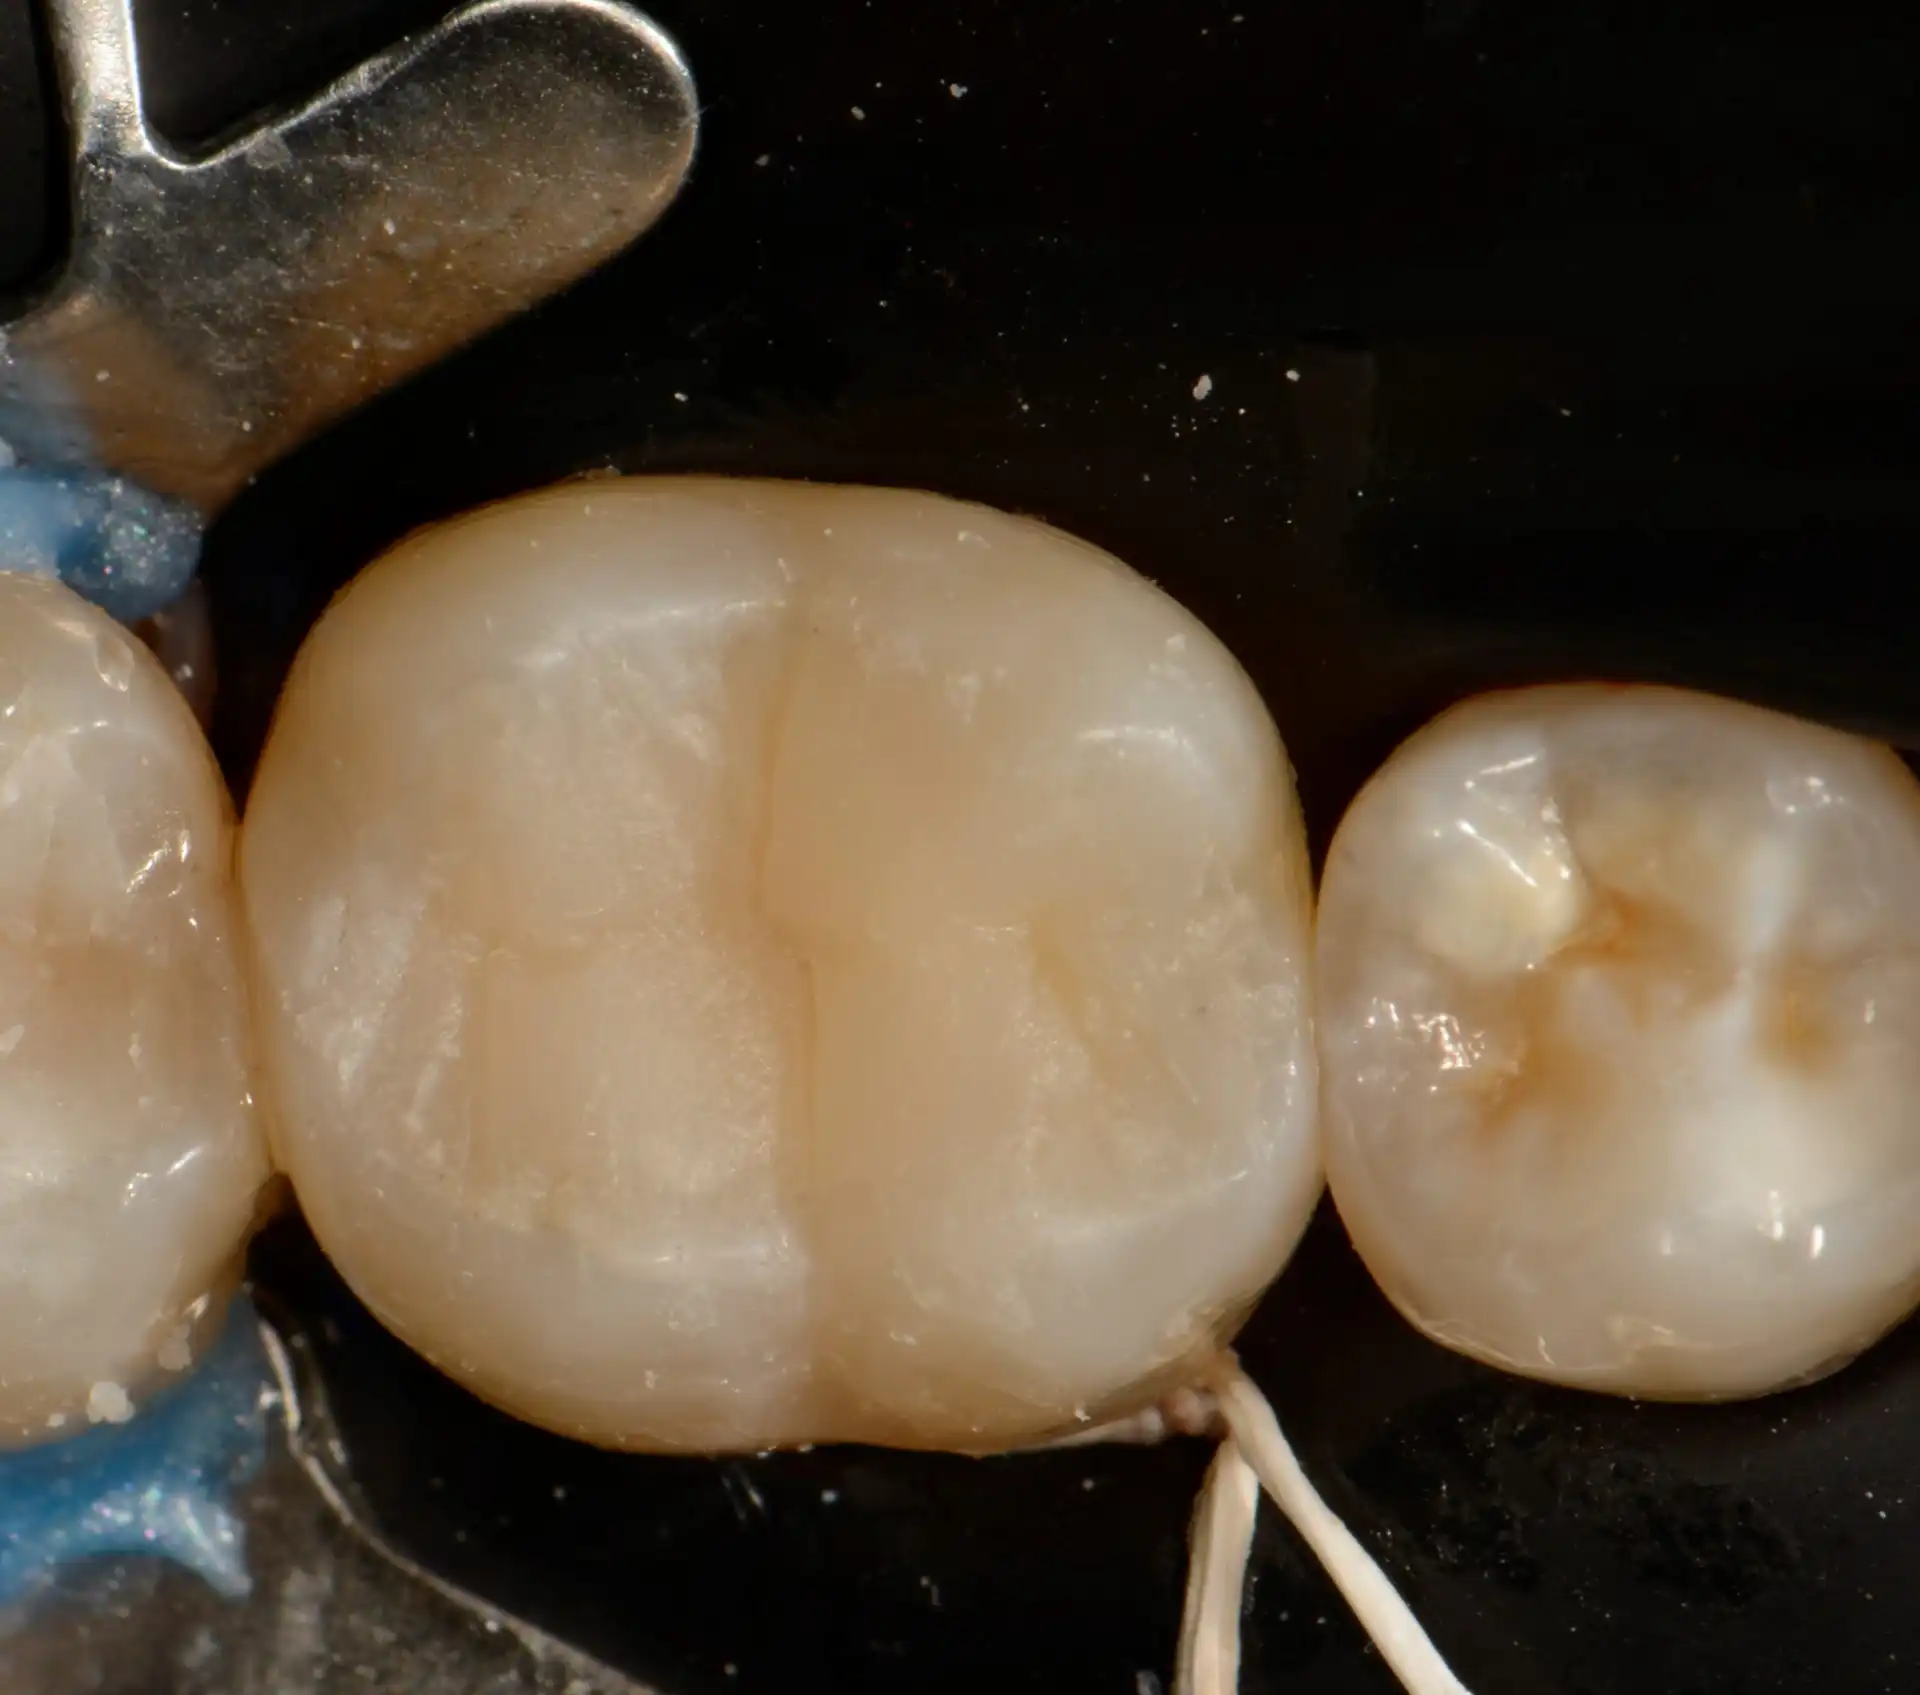

Confira este caso clínico de restauração dentária posterior, terceiro molar, com a resina tipo Bulk da 3M.